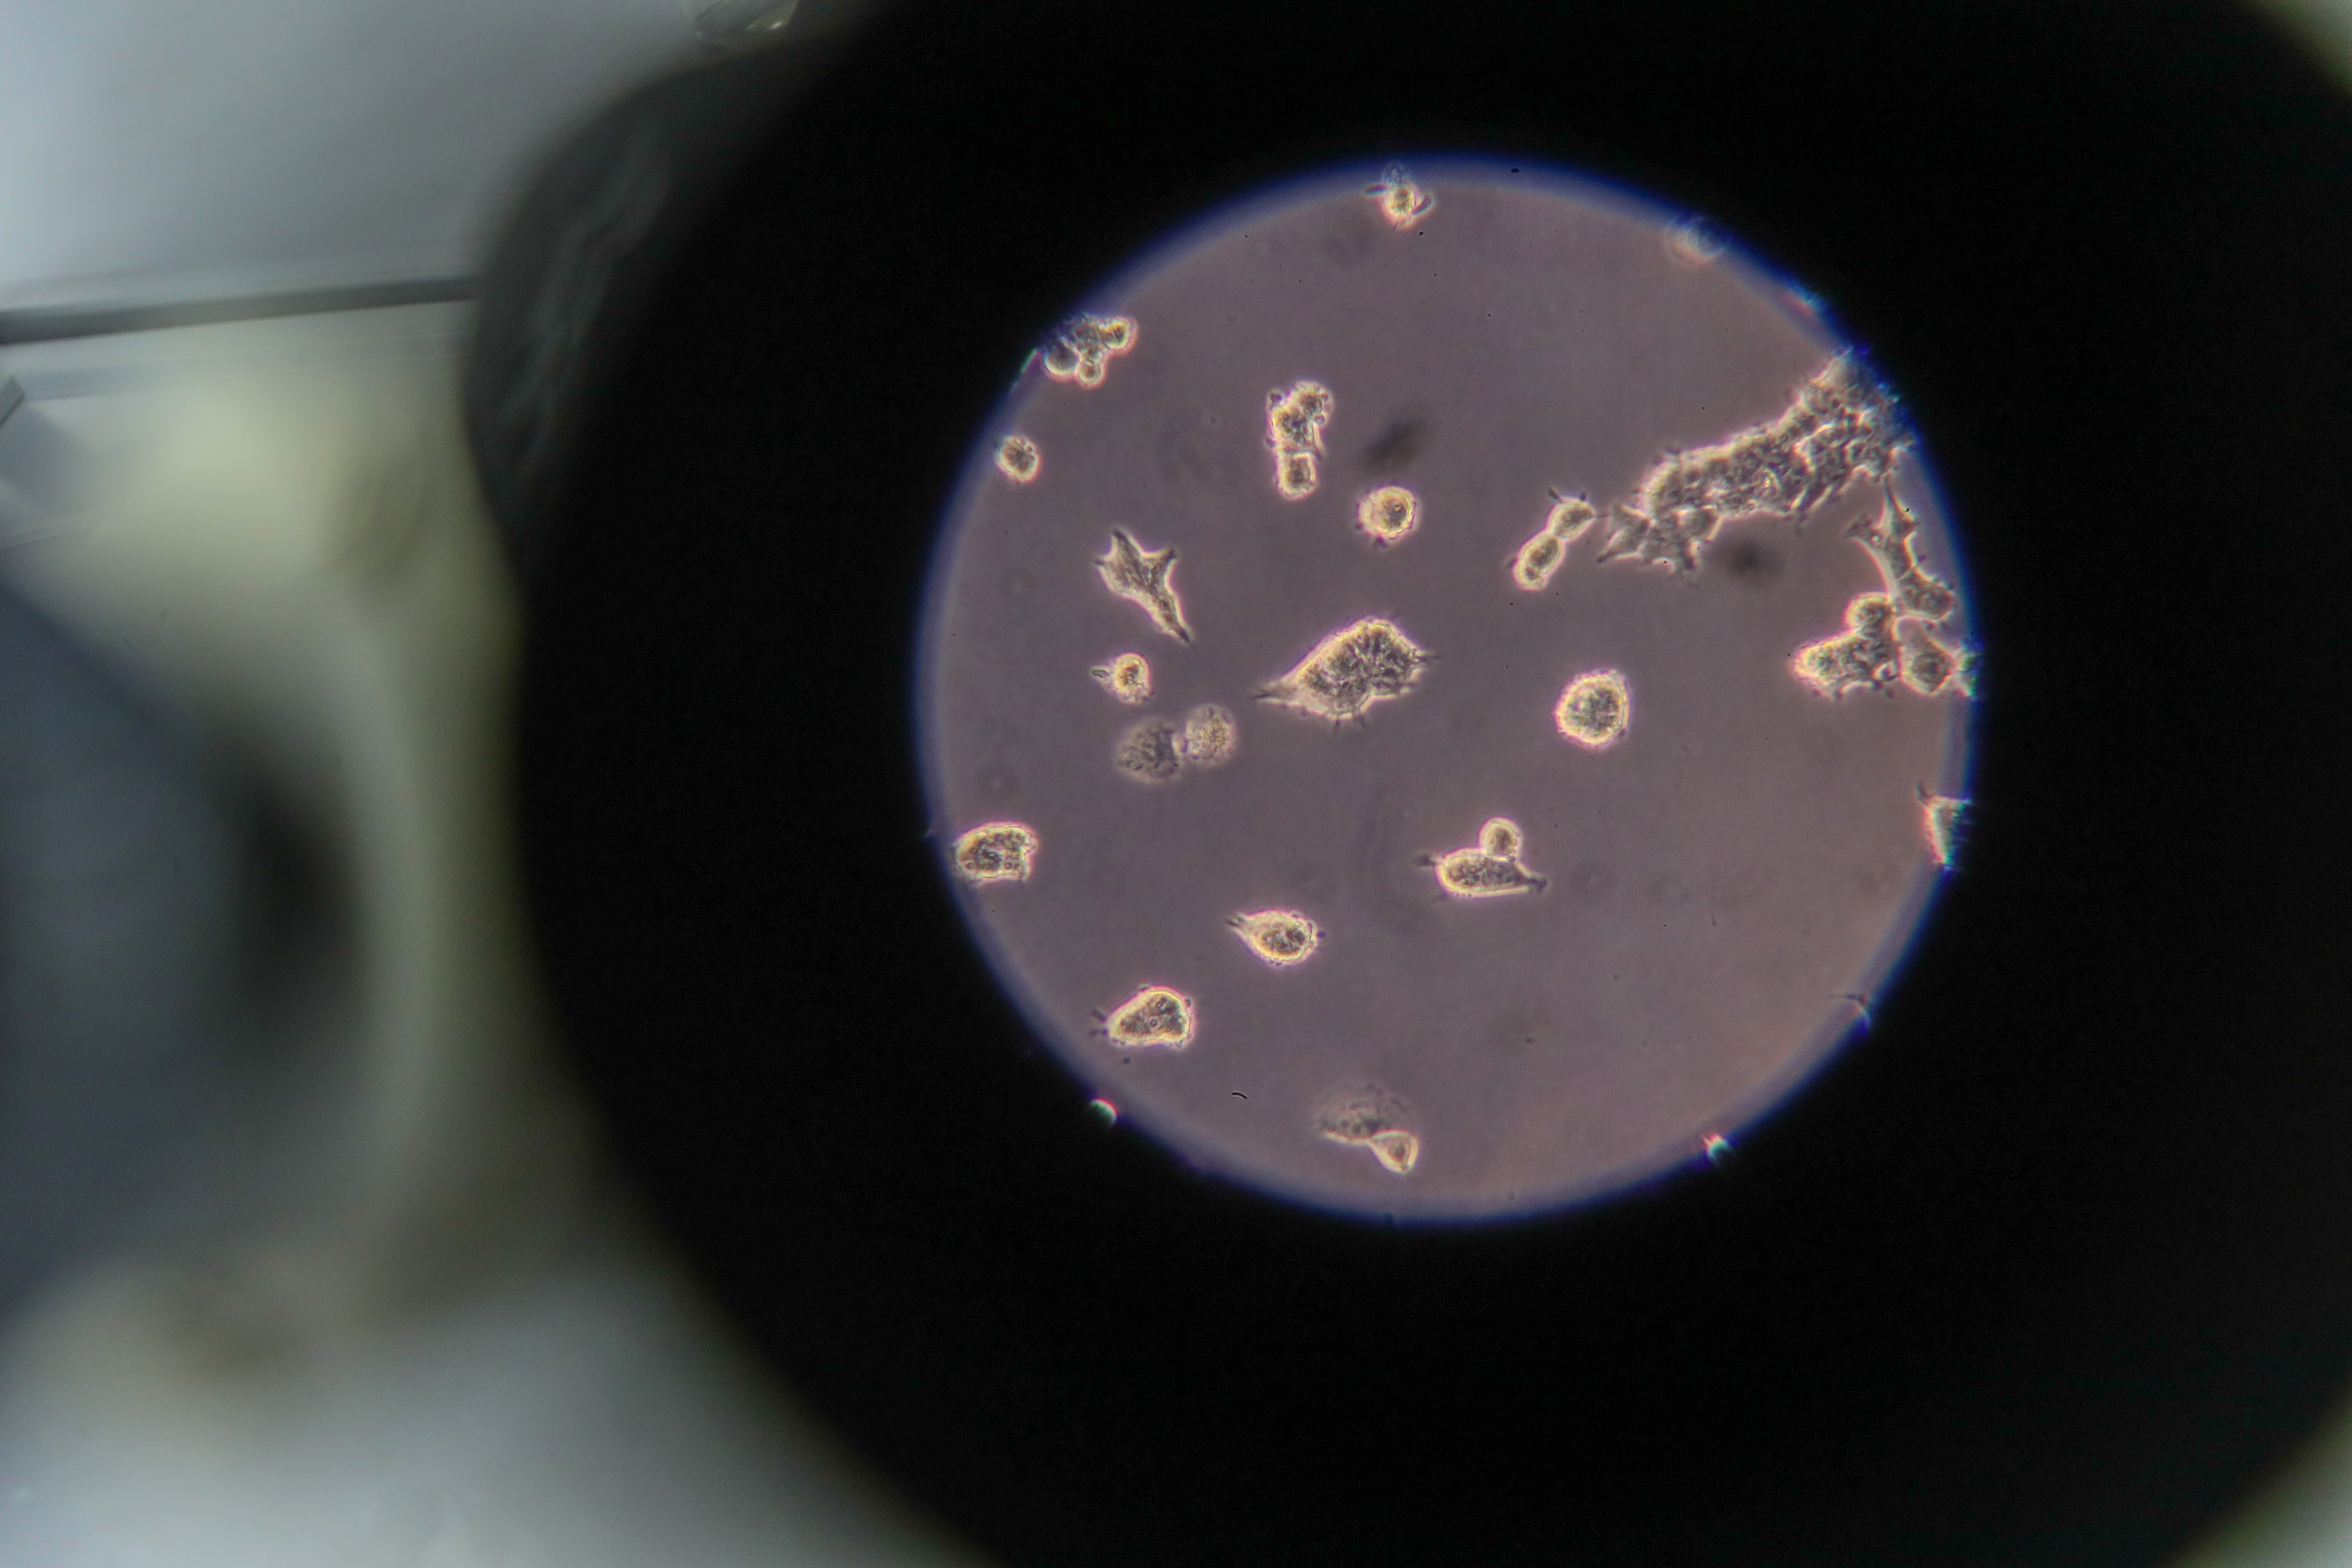

MOSCOW, April 27. /TASS/. The State Scientific Center of Virology and Biotechnology "Vector," located in Novosibirsk, hopes to obtain a sample of the Indian strain of the novel coronavirus soon. The strain will take about two months to examine, the center told TASS.

"The Vector center is one of the World Health Organization’s 26 reference laboratories for COVID-19. We hope to obtain a sample of the Indian strain of the virus from our foreign counterparts soon. Comprehensive examination of the new strain’s properties, including the effectiveness of the vaccine against it, will take about two months," the news release runs.